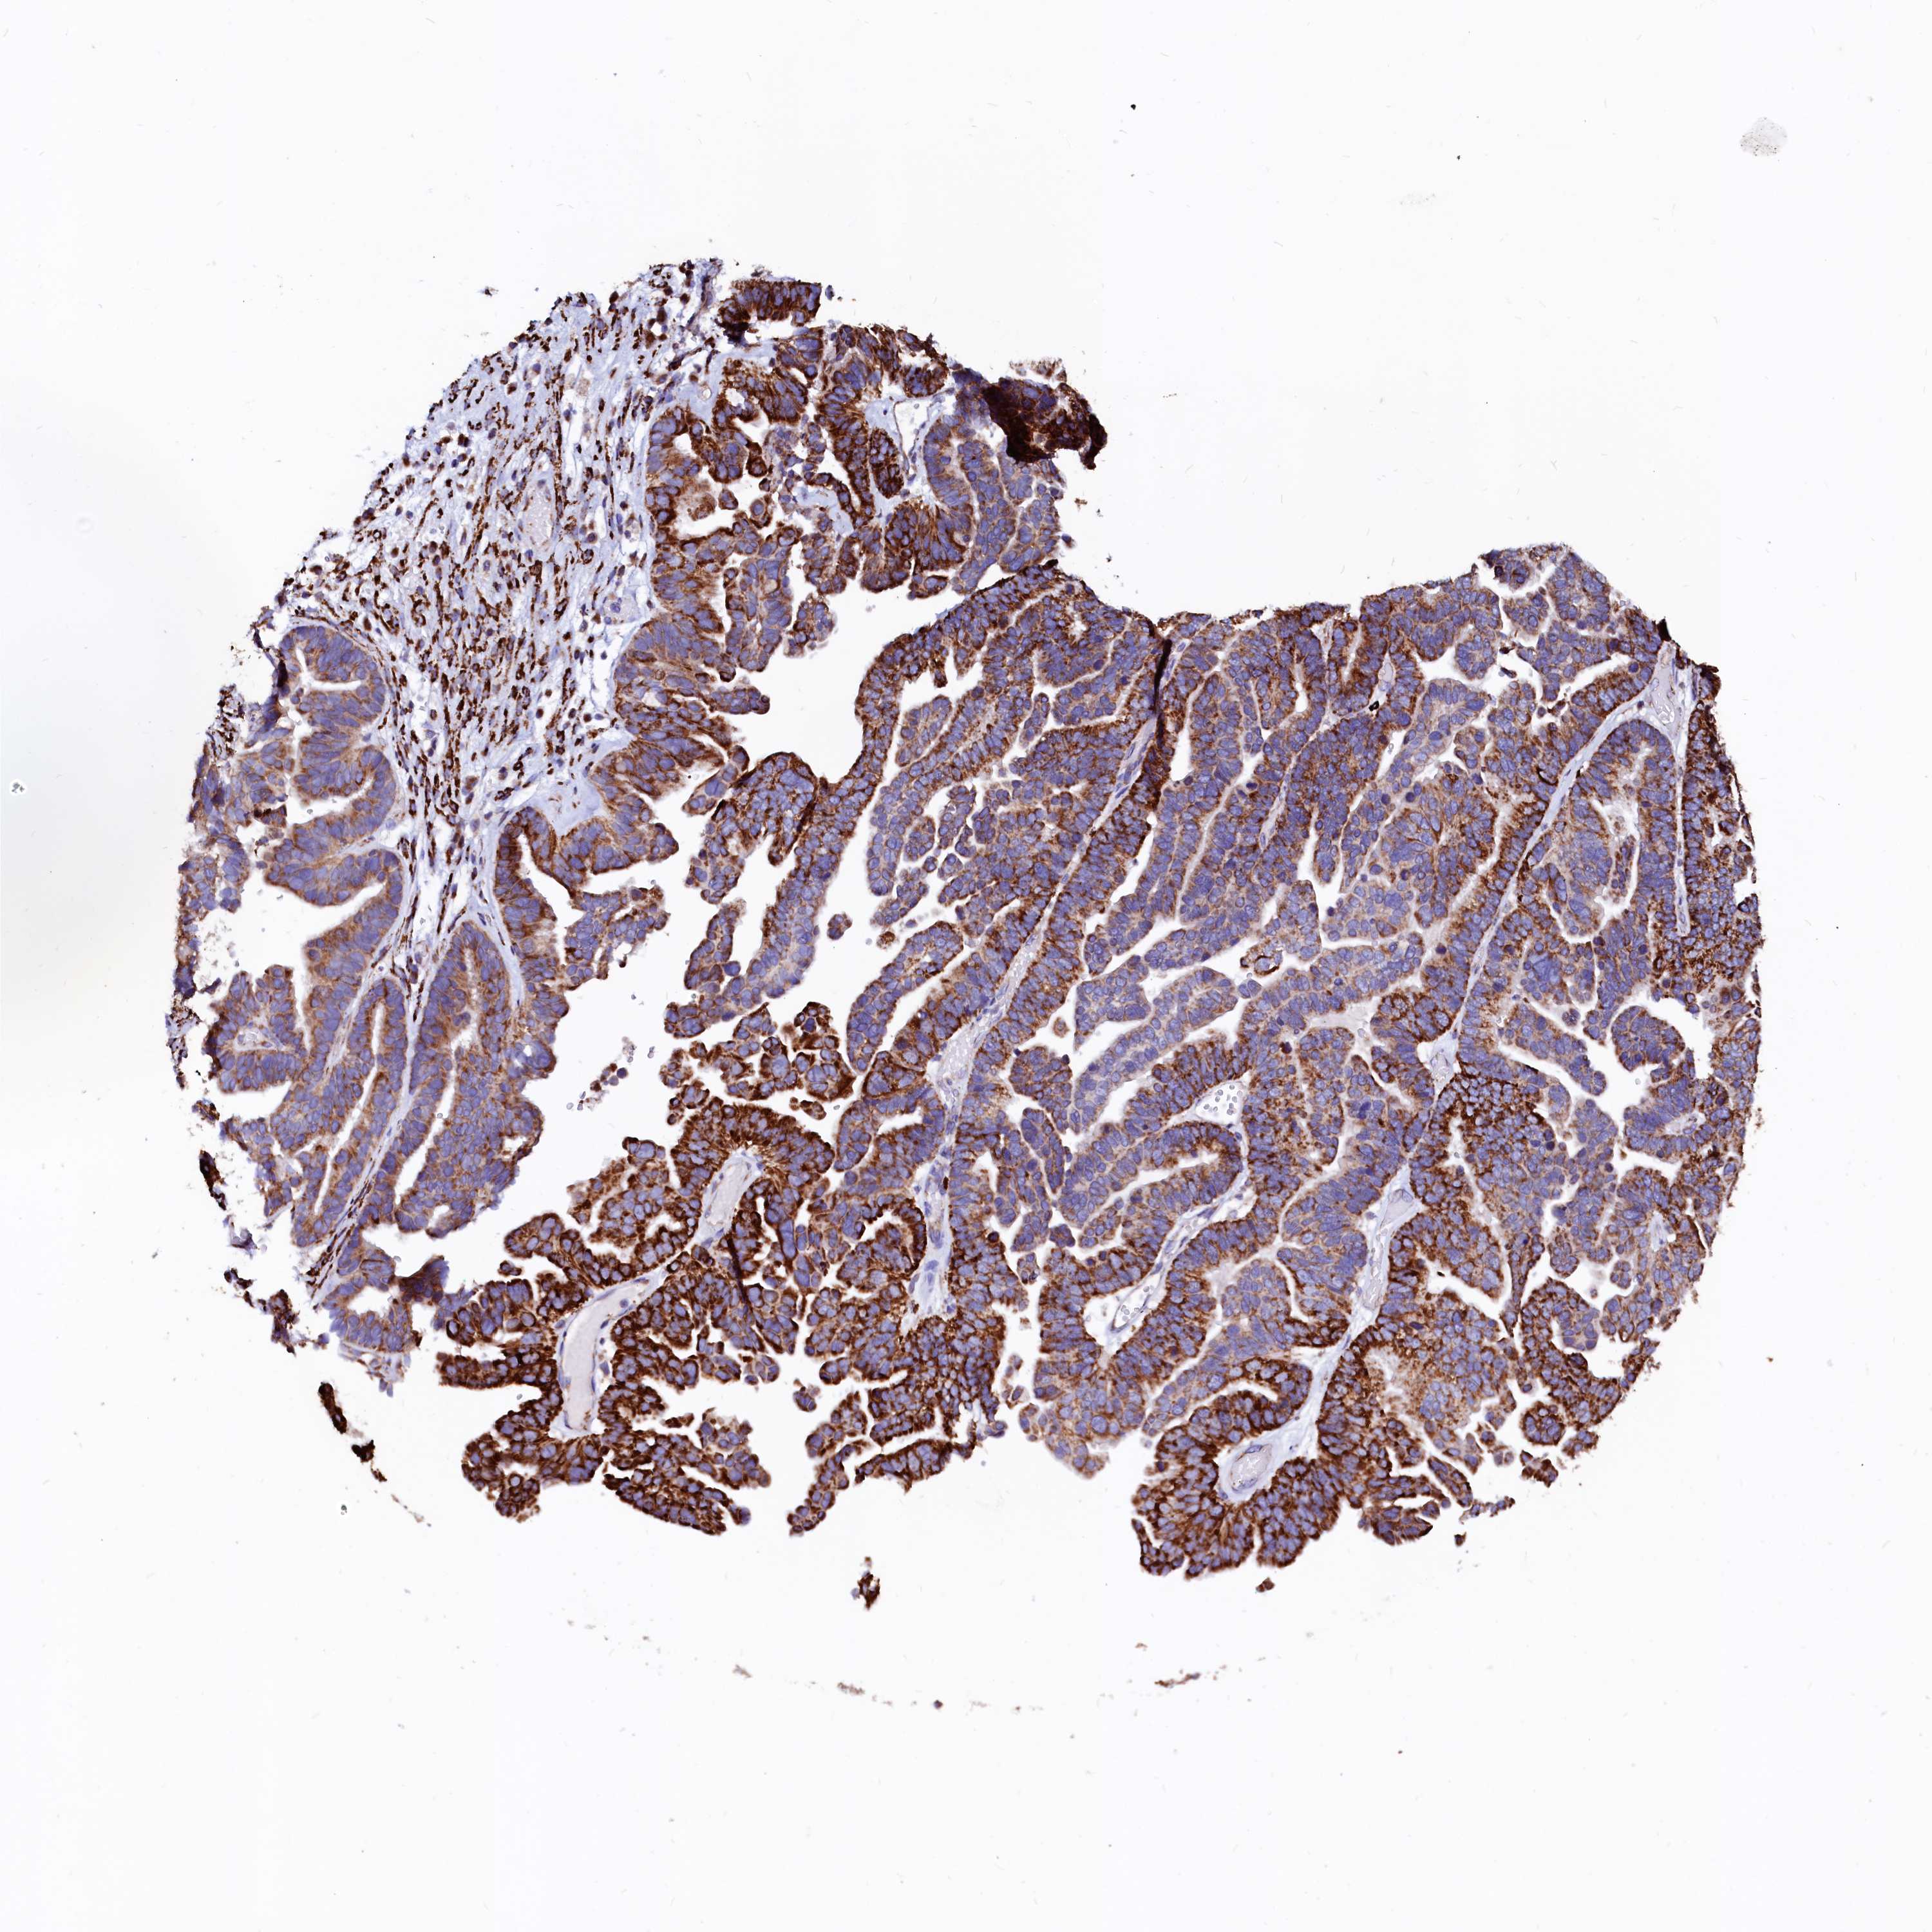

OVARIAN CANCER - Protein expressioni

A mouse-over function shows sample information and annotation data. Click on an image to view it in a full screen mode. Samples can be filtered based on level of antibody staining by selecting one or several of the following categories: high, medium, low and not detected. The assay and annotation is described here.

Note that samples used for immunohistochemistry by the Human Protein Atlas do not correspond to samples in the TCGA dataset.

Antibody stainingi

Antibody staining in the annotated cell types in the current human tissue is reported as not detected, low, medium, or high, based on conventional immunohistochemistry profiling in selected tissues. This score is based on the combination of the staining intensity and fraction of stained cells.

Each image is clickable and will lead to virtual microscopy that enables deeper exploration of all samples and also displays staining intensity scores, fraction scores and subcellular localization as well as patient and tissue information for each sample.

Antibody HPA002328

Antibody CAB037200

Staining

High

Medium

Low

Not detected

Intensity

Strong

Moderate

Weak

Negative

Quantity

>75%

75%-25%

<25%

None

Location

Nuclear

Cytoplasmic/membranous

Cytoplasmic/membranous,nuclear

Cystadenocarcinoma, mucinous, NOS

Carcinoma, endometroid

Cystadenocarcinoma, serous, NOS

Carcinoma, NOS